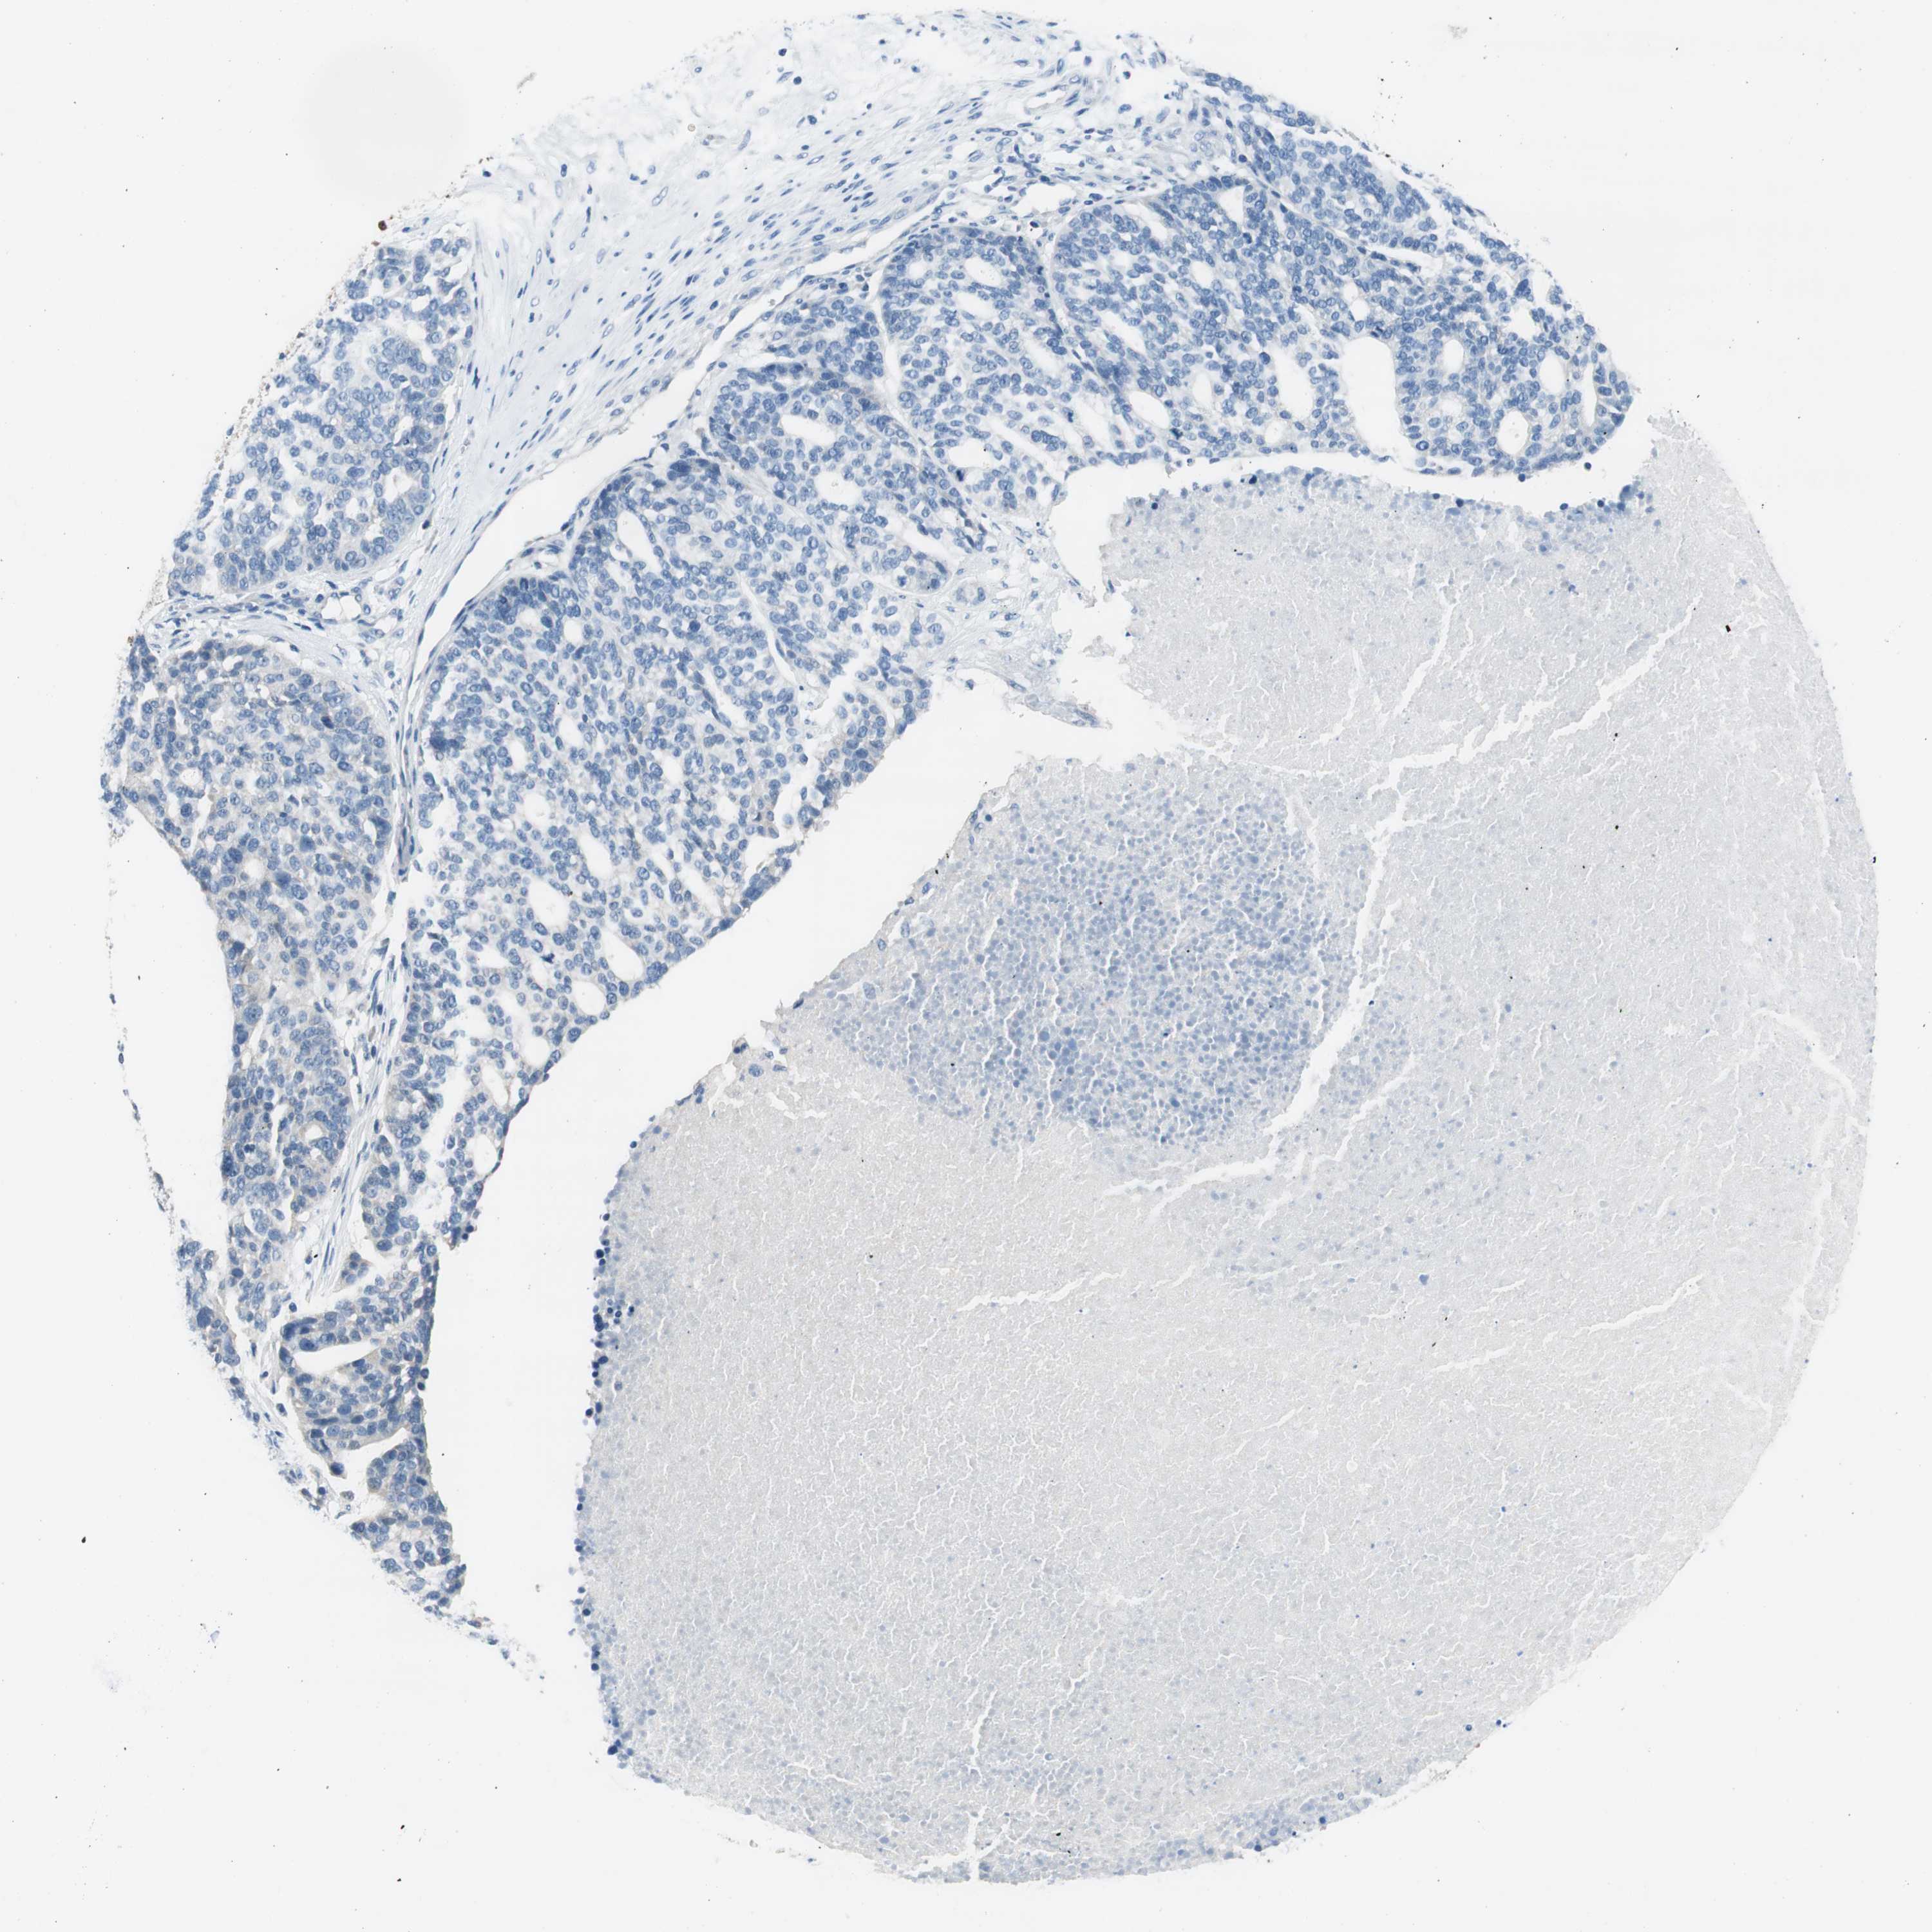

OVARIAN CANCER - Protein expressioni

A mouse-over function shows sample information and annotation data. Click on an image to view it in a full screen mode. Samples can be filtered based on level of antibody staining by selecting one or several of the following categories: high, medium, low and not detected. The assay and annotation is described here.

Note that samples used for immunohistochemistry by the Human Protein Atlas do not correspond to samples in the TCGA dataset.

Antibody stainingi

Antibody staining in the annotated cell types in the current human tissue is reported as not detected, low, medium, or high, based on conventional immunohistochemistry profiling in selected tissues. This score is based on the combination of the staining intensity and fraction of stained cells.

Each image is clickable and will lead to virtual microscopy that enables deeper exploration of all samples and also displays staining intensity scores, fraction scores and subcellular localization as well as patient and tissue information for each sample.

Antibody HPA008055

Staining

High

Medium

Low

Not detected

Intensity

Strong

Moderate

Weak

Negative

Quantity

>75%

75%-25%

<25%

None

Location

Nuclear

Cytoplasmic/membranous

Cytoplasmic/membranous,nuclear

Cystadenocarcinoma, serous, NOS

Carcinoma, endometroid

Carcinoma, NOS

Cystadenocarcinoma, mucinous, NOS